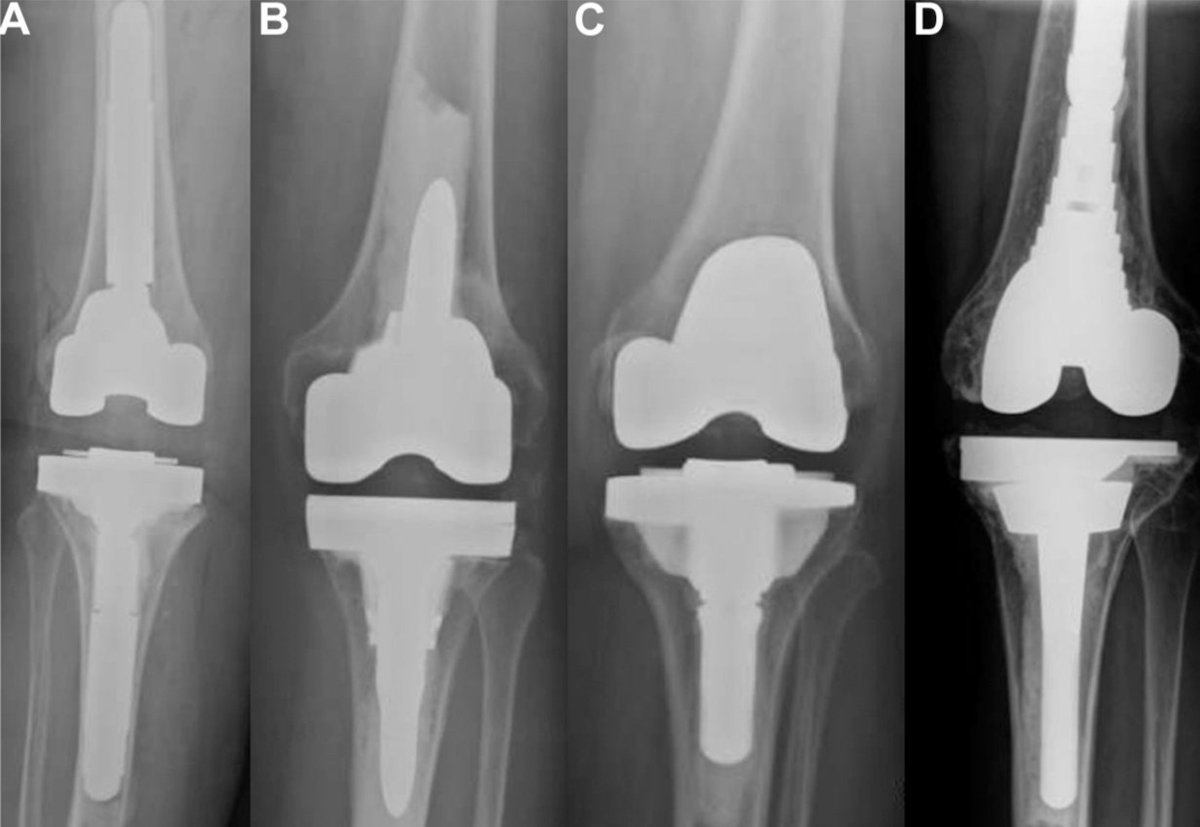

Patients who had symmetric tibial augment constructs exhibited similar rates of radiolucency but higher survivorship compared to those with asymmetric constructs overall. However, when metaphyseal cones were utilized, survivorship was equivalent. https://t.co/ForMz4dU8s